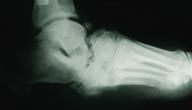

كسور العظام

تعتبر كسور العظام من المشاكل التي قد يمر بها أي شخص خلال حياته والتي قد تحصل نتيجة تأثير قوة معينة أو الإجهاد، مع ذلك فإن بعض كسور العظام قد تنجم نتيجة الإصابة ببعض الحالات الصحية التي تضعف العظام كهشاشة العظام أو نتيجة الإصابة ببعض أنواع السرطان أو نتيجة حدوث خلل في مرحلة ما من تكون العظم ويعرف هذا النوع من الكسور باسم الكسر المرضي، ويمكن أن تتراوح كسور العظام في شدتها لتشمل الصدوع الرقيقة إلى الكسر الكامل لمحيط العظم، وقد تحدث الكسور بشكل عرضي أو طولي أو في عدة أماكن مختلفة، ويستعرض المقال العديد من المعلومات حول كسور العظام وأنواعها وطرق الوقاية منها.[١]

تتعدد أنواع كسور العظام وتختلف عند حدوثها من شخص إلى آخر اعتمادًا على سبب حدوثها ومقدار شدة الحادث المسببة لها وغيرها من العوامل، كما يتم تحديد نوع الكسر من قبل الأطباء لاختيار العلاج الأنسب والذي يختلف باختلاف أنواعها، ومن أبرز أنواع كسور العظام ما يأتي:[٢]

• الكسر القلعي: يحدث الكسر القلعي نتيجة زيادة الضغط الذي تولده العضلات أو الأوتار على العظم.

• تفتت العظم: في هذا النوع من الكسور يلاحظ تفتت العظم إلى مجموعة من القطع.

• الكسر المسحوق: يحدث هذا النوع نتيجة الإصابة بهشاشة العظام التي تؤثر بشكل عام على العظام الإسفنجية في العمود الفقري.

• الكسر نتيجة الخلع: يؤدي حدوث خلع في المفصل إلى الإصابة بكسر في أحد العظام المفصلية.

• الكسر الجزئي: يحدث هذا النوع لدى الأطفال بشكل شائع نتيجة مرونة وليونة العظام في مرحلة الطفولة مما يؤدي إلى كسر العظم جزئيًا من جانب.

• الكسور الشعرية: يعرف هذا النوع بأنه شعر أو كسر جزئي للعظم.

• الكسر الناجم عن التأثر بكسر آخر: يحدث هذا النوع عند انتقال شظية من العظم المكسور إلى عظام أخرى محيطة بها.

• الكسور داخل المفاصل: يحدث هذا النوع نتيجة امتداد الكسر إلى سطح المفصل.

• الكسور الطولية: يحدث هذا الكسر بشكل طولي في العظام.

• الكسور المائلة: يكون الكسر في هذا النوع مائلًا إلى المحور الطويل من العظم.

• الكسور المرضية: هي الكسر الناجمة عن الإصابة بأمراض تؤدي إلى إضعاف العظم.

• الكسور الحلزونية: هي الكسور الناجمة عن لف جزء من العظم.

• الكسر نتيجة الإجهاد: يحدث هذا النوع نتيجة القيام بمجهود عالي وغالبًا ما يحدث بين الرياضيين.

• الكسر المشبك: يؤدي هذا النوع إلى الإصابة بتشوه في العظام دون التشقق فيها وغالبًا ما يصاب الأطفال به.

• الكسر المستعرض: هو الكسر الذي يؤثر على العظم بشكل مباشر ومستقيم.